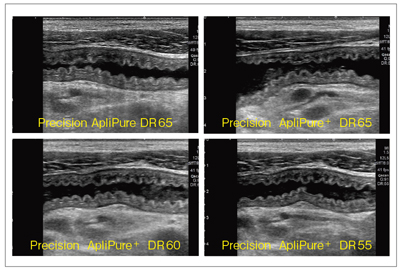

(2)Precision Imaging,ApliPure+

Aplio500では,Precision ImagingとApliPure+がHDBでさらに高画質化された。Precision は,ノイズ成分を低減し,コントラスト分解能や均一性,組織の連続性を高め,ApliPure+は,コンパウンド技術による画像の鮮明化や,スペックルノイズの低減,また,深部感度の向上を可能にする。

図2は,下行結腸がん症例での,いわゆるpseudo kidney signを呈した画像である。Precision Imaging によるAplioXG画像(図2 a)では,画質の視認性は向上するが白さが強調されやや誇張され過ぎた画質となっていたが,Aplio500(図2 b)では白さが抑えられ,辺縁がきれいにつながったイメージに表現され,Precision Imagingの持つ特徴をより生かしたものに改善されている。

図2 Precision ImagingとApliPureを適応した下行結腸がん症例

次に,急性虫垂炎症例のAplioXGとAplio500の比較画像を図3に提示する。図3上段はコンベックス型探触子(3.5MHz),中段はコンベックス型探触子(6.0MHz)のPrecision ImagingとApliPureで処理を行った画像だが,Aplio500ではスムーズな処理で鮮明に描出されていることがわかる。さらに,高周波リニア型探触子の8.0MHz(図3下段)においては,AplioXGでは表現できなかった虫垂壁の層構造と,内部に貯留した液体の性状が識別できるなど,Aplio500では「見えなかったものが見える!」と言えるほどに画質が向上していることがわかる。

図3 急性虫垂炎のAplioXG(a)とAplio500(b)の画像比較

以上のように,Aplio500は,Precision ImagingやApliPure,ApliPure+,TSOのさまざまな組み合わせが可能である。組み合わせにより,空間分解能,コントラスト分解能やリアルタイム性が変化するため,検査の目的(何を見るか,どこを見るか)に合わせて選択することが重要である。